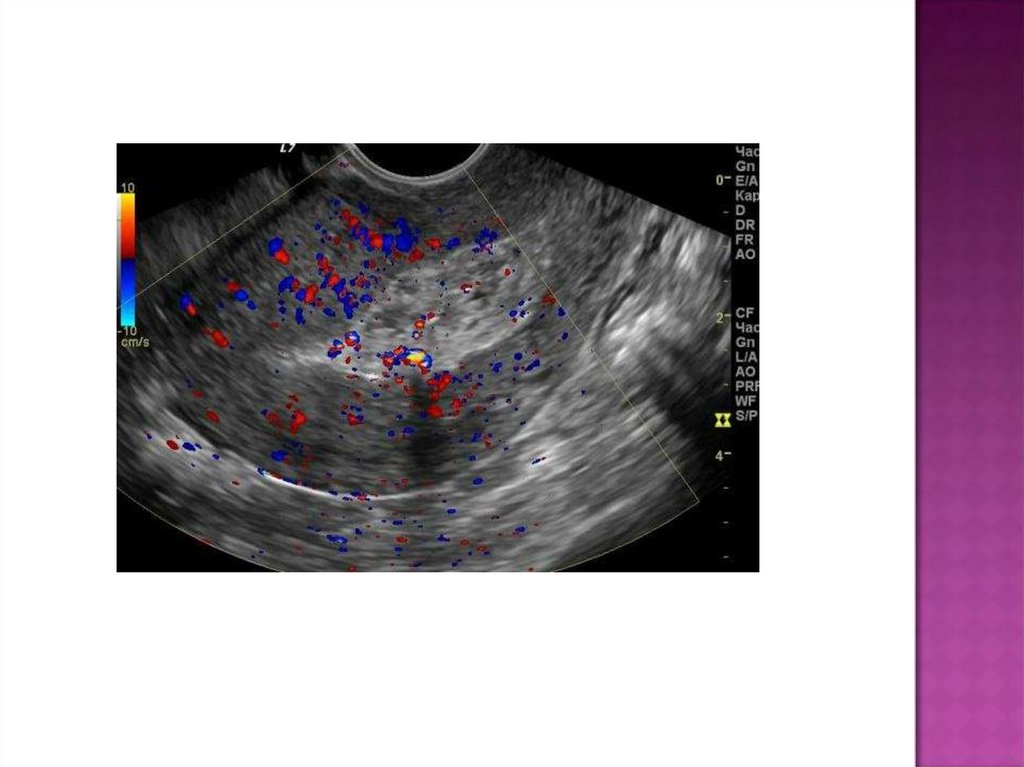

УЗИ:

УЗИ позволяет заподозрить данное заболевание по

сочетанию признаков:

·субинволюция матки;

·расширенная полость матки со множеством точечных

эхопозитивных включений (пузырьки газа);

·выраженный гипоэхогенный контур полости матки

(инфильтрация).

С помощью УЗИ можно обнаружить фрагменты последа

(эхопозитивные наложения на стенках матки).